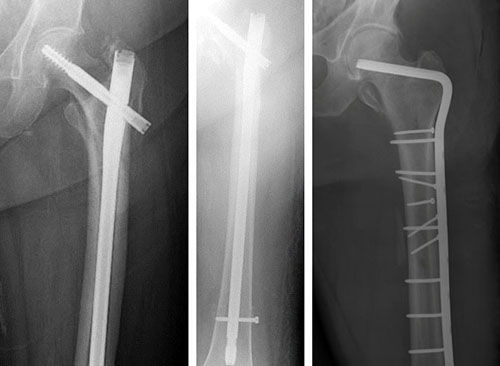

They are treated surgically with an intramedullary nail into the shaft of the femur and a screw placed through the nail into the femoral head.

To keep the bones from rotating around the nail or from shortening (telescoping) on the nail, additional screws may be placed at the lower end of the nail near the knee. These are called interlocking screws.

In some cases, your surgeon may choose to use a compression screw with a long side plate instead of a nail.

treatment options for subtrochanteric fracture

X-rays show treatment options for a subtrochanteric fracture: (Left) Intramedullary nail and screw, (Center) An interlocking screw has been placed at the lower end of the femur to prevent the bone from shortening. (Right) Side plate and compression screws.